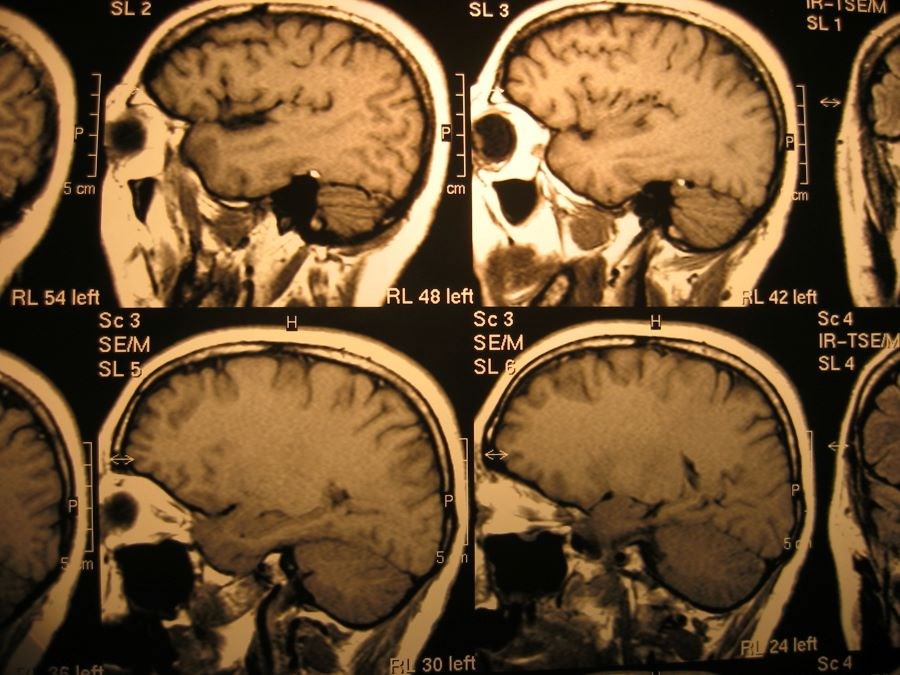

Dat schrijft UMC Utrecht op haar website. De onderzoekers richtten zich met name op de hippocampus. Dat is een hersengebied dat een rol speelt bij het geheugen en het regulieren van emoties. Depressie gaat vaak gepaard met een verkleining van dit gebied. Na ECT-behandelingen is op MRI-beelden een toename in volume zichtbaar.